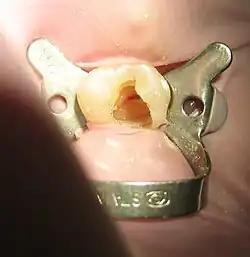

La técnica utilizada para aplicar el dique dental se selecciona según el diente que requiera tratamiento. Se pueden utilizar varias técnicas, incluido el aislamiento de un solo diente, el aislamiento de múltiples dientes o la técnica de dique dividido. El dique dental se prepara perforando uno o más orificios en la lámina del dique dental para permitir el aislamiento del número apropiado de dientes necesarios para el procedimiento dental. A continuación, se aplica el dique dental al diente, se fija en su lugar con una abrazadera de metal o plástico flexible (elegida según el diente y la zona a la que se aplicará). Idealmente, la abrazadera se ajustará perfectamente alrededor del diente a lo largo del margen de la encía, estabilizando el dique dental y evitando la contaminación del área de trabajo debido a la entrada de saliva. Las personas pueden experimentar malestar subjetivo debido a la sensación apretada de la abrazadera del dique, por lo tanto, se puede aplicar anestésico tópico (líquido o gel) a la encía a discreción del operador antes de aplicar el dique dental.[6]

El dique dental se ancla alrededor de la corona del diente usando una abrazadera de metal para sellar y asegurar la lámina de dique de goma al diente o dientes que están recibiendo tratamiento durante el procedimiento dental. Las abrazaderas vienen en una variedad de formas y tamaños que se adaptan a la anatomía de los diferentes dientes. Antes de colocar el dique en la boca, los profesionales dentales pueden optar por asegurar hilo dental alrededor de las abrazaderas; esto actúa como un ancla para prevenir la aspiración o la deglución. También puede proporcionar un punto de referencia para que el médico pueda visualizar y recuperar la pinza si se desprende del diente o del fórceps de dique.[12]